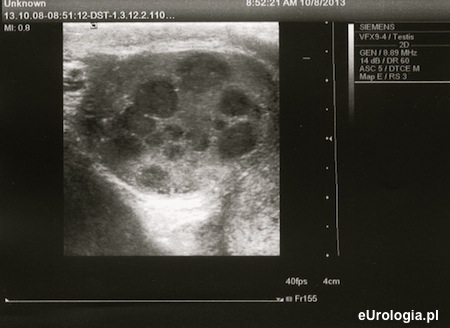

Badanie USG jąder charakteryzuje blisko 95% skutecznością w wykrywaniu guzów jądra. W badaniu ultrasonograficznym guzy jądra widoczne są jako hipoechogeniczne kuliste obszary o jednorodnej echostrukturze z dobrze widocznymi granicami. Czasami w obrębie guza mogą być widoczne przestrzenie płynowe. Guzy jądra mogą być jednoogniskowe lub wieloogniskowe. W opcji kolorowego Dopplera w obrębie guza widoczny jest wzmożony przepływ w obrębie patologicznej zmiany.

Fot. Rak jądra - liczne ogniska guza w USG moszny